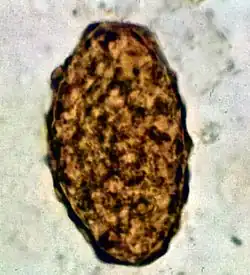

Fertile egg in human faeces (detail)

Infertile egg

Ascaris lumbricoides is characterized by its great size. Males are 2–4 mm (0.08–0.2 in) in diameter and 15–31 cm (5.9–12 in) long. The male's posterior end is curved ventrally and has a bluntly pointed tail. Females are 3–6 mm (0.1–0.2 in) wide and 20–49 cm (7.9–19 in) long. The vulva is located in the anterior end and accounts for about one-third of its body length. Uteri may contain up to 27 million eggs at a time, with 200,000 being laid per day. Fertilized eggs are oval to round in shape and are 45–75 μm (0.0018–0.0030 in) long and 35–50 μm (0.0014–0.0020 in) wide with a thick outer shell. Unfertilized eggs measure 88–94 μm (0.0035–0.0037 in) long and 44 μm (0.0017 in) wide.[9]